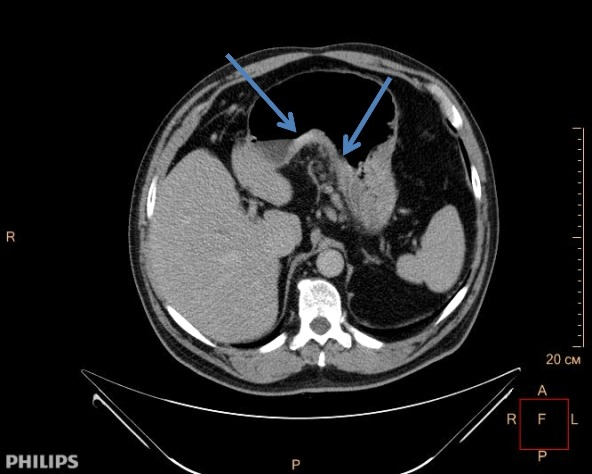

- Компьютерная томография. Дает возможность получить детальнейшие изображения структур желудка. Процедура абсолютно безболезненна и длится не долее 10-15 минут.